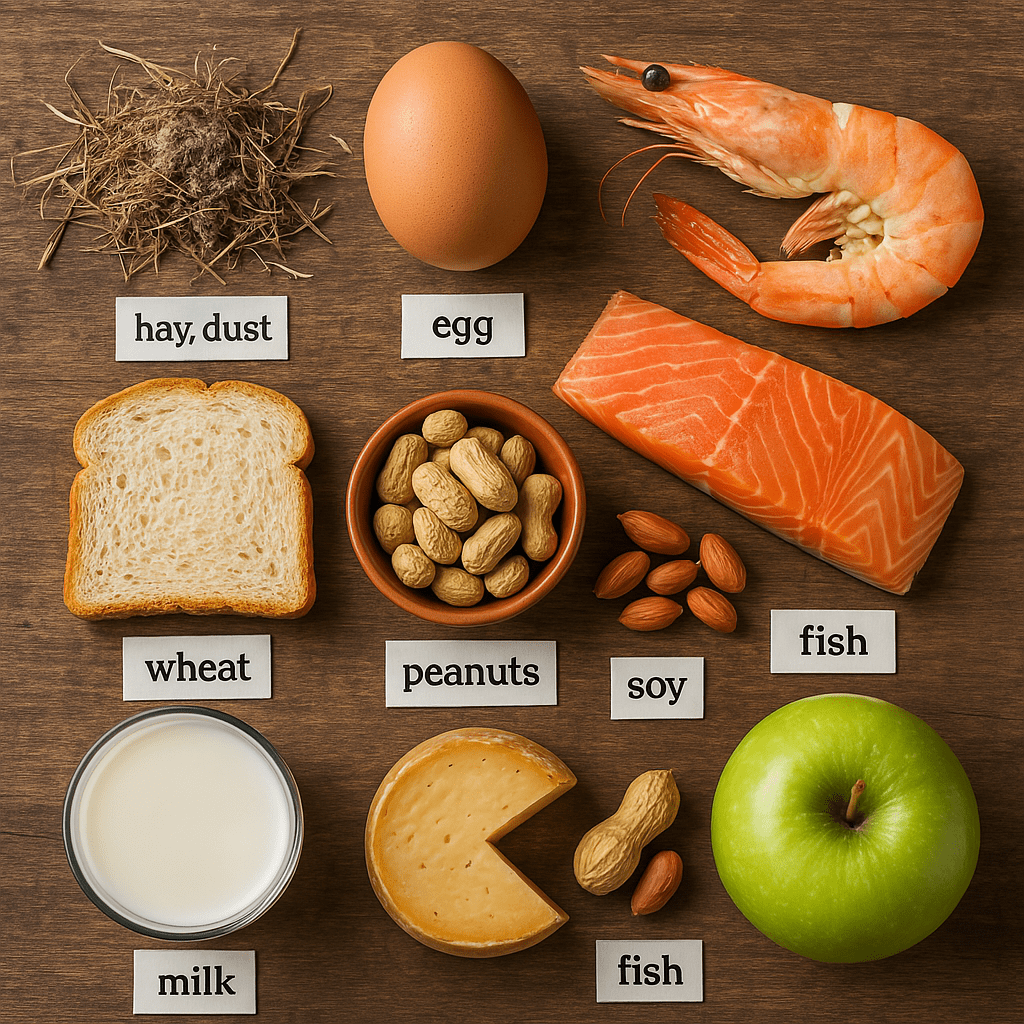

Eliminace intolerancí

Eliminace potravinových intolerancí-Pomáhá odhalit a harmonizovat reakce těla na určité potraviny, které mohou způsobovat záněty, zadržování vody nebo nadýmání.